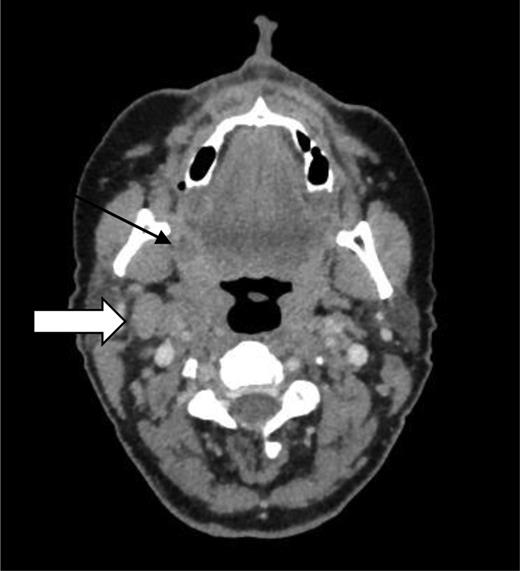

On imaging with computed tomography (CT) of the neck and chest, an asymmetrically enhancing soft tissue mass was seen in the right glossotonsillar sulcus, with associated ipsilateral right-sided level 2A lymphadenopathy (Fig. 1). Positron emission tomography (PET) demonstrated hypermetabolism in the right glossotonsillar sulcus, which was consistent with the primary site and evidence of distant metastases (Fig. 2). The patient was reviewed in the Head and Neck clinic and was staged on imaging as T1 N2b M0.

CT showing a primary tumour in the right glossotonsillar sulcus (black arrow) and lymphadenopathy (white arrow).